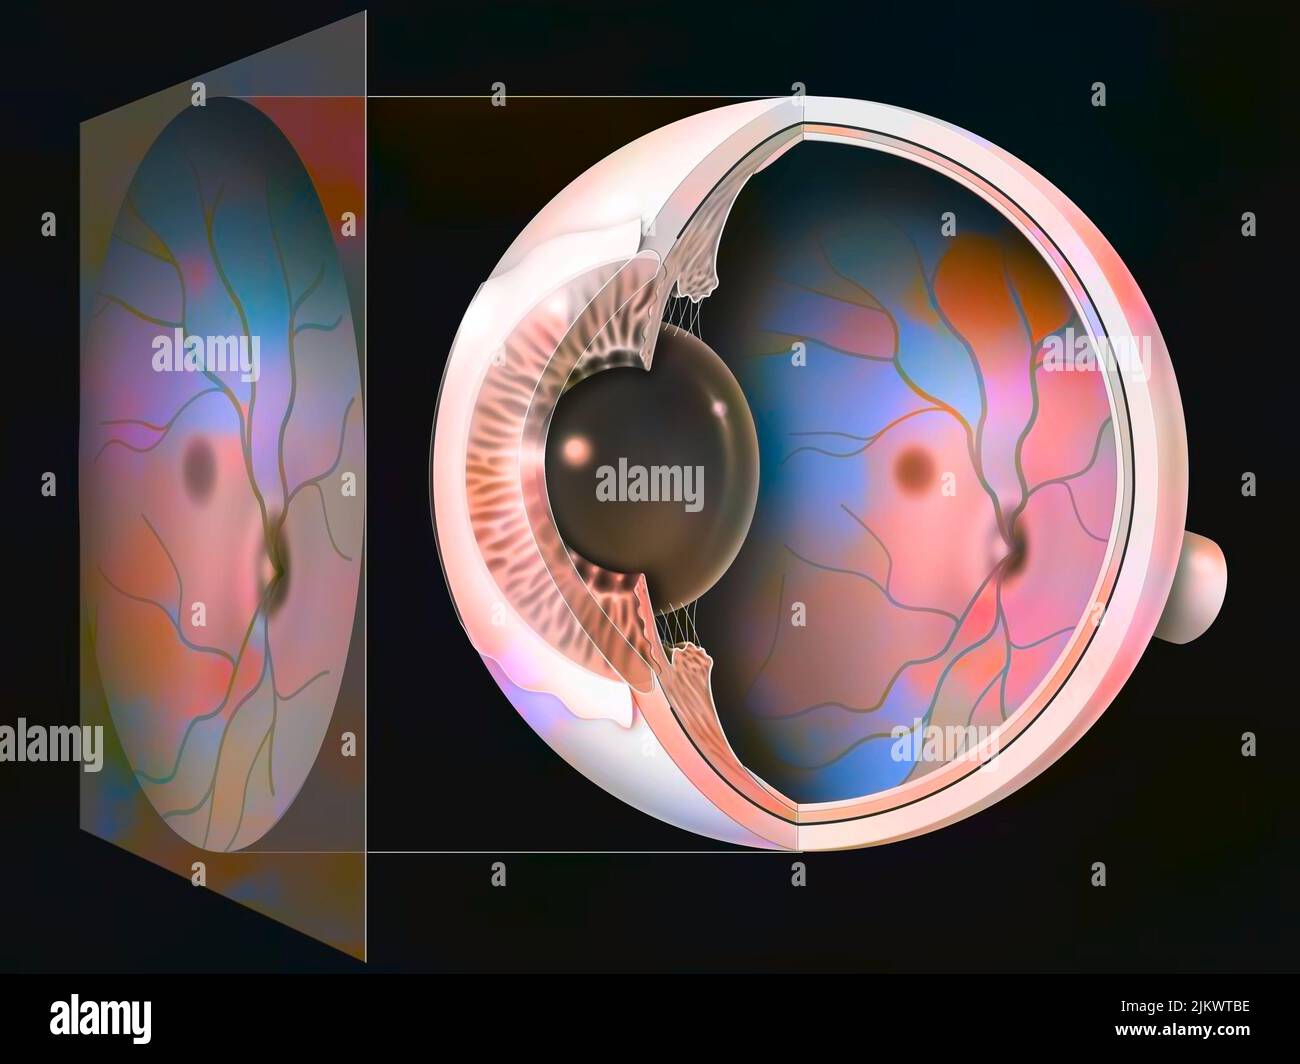

RF2JKWT9A–Oeil, cataracte, phacoémulsification - étape 2: Consiste à casser la lentille avec une sonde.